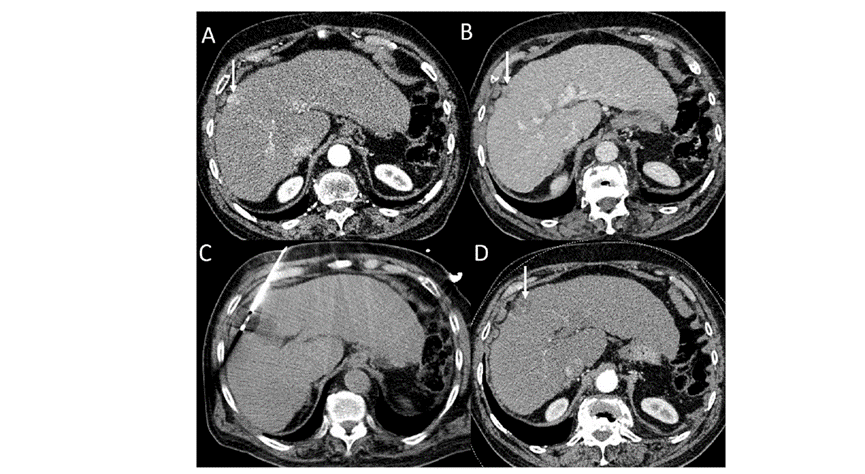

51岁男性患者,肝移植后复发病例

(a) 射频消融后在病变边缘显示残余增强。

(b) 冷冻消融术中影像显示冰球完全覆盖病变。

(c) 19个月后随访,没有发生局部肿瘤进展。